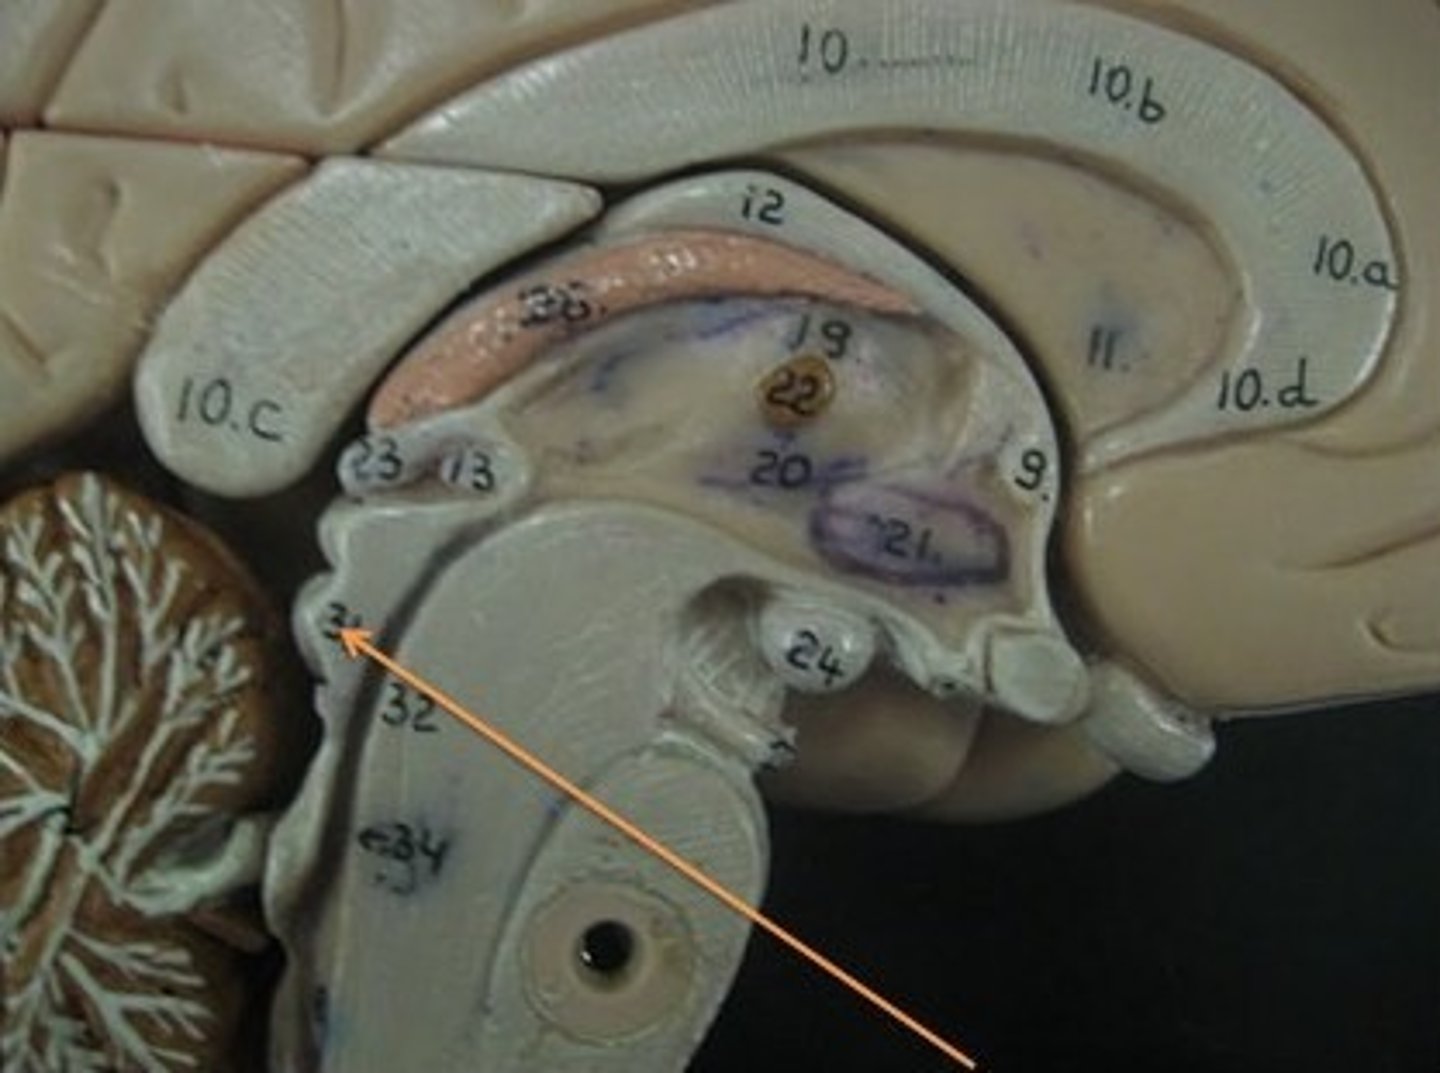

brain stem

Includes the mid brain, pons, and medulla oblongata.

midbrain

corpora quadrigemina,connector of cerebrum, diencephalon, and cerebellum to spinal cord. Connector in central nervous system.

corpora quadrigemina

Also known as the tectal plate. Consists of the superior colliculi and the inferior colliculi.

superior colliculi

bumby part on opposite side of pituitary gland. Top one. Responsible for visual reflex (track objects visually). If we see something in peripheray, we can turn towards object. Instinctive reflex.

inferior colliculi

bumpy part on opposite of pituitary gland. Bottom one. 31 auditory tracking. If we hear a loud noise, we can move toward it.

pons

contains parts of respiratory center. Plays a role in controlling breathing rate and depth.

medulla oblongata

has a cardiac center. Plays a role in influencing heart rate and the force of the contractions in the heart. In response to changes in blood pressure and oxygen levels.

- vasomotor center - helps to control blood pressure. Sends out signals that causes vasoconstriction or vasodilation of blood vessels. Contains parts of respiratory center.

- initiates inspiration and respiration.

cerebellum

cerebellar hemispheres, cerebellar cortex, and arbor vitae.-

the little brain.

- Function: coordinates all voluntary movements. Ability to ride a bike, dance, anything complicated that calls for coordinating movement between left and right sides with skeletal muscles.

- Ability to move joints in a coordinated fashion- cerebellum in charge.

cerebellar hemispheres

divided by vermis.

cerebellar cortex

outer covering of cerebellum - gray matter.

arbor vitae

"tree of life" white matter in cerebellum.

ventricles

cavities in the brain. Includes lateral ventricles - right and left, third ventricle, fourth ventricle, cerebral aqueduct, and choroid plexus.

third ventricle

in the area where the hypothalamus is.

fourth ventricle

located beneath the arbor vitae in the cerebellum.

cerebral aqueduct

connector between third and fourth ventricle in front of colliculi.